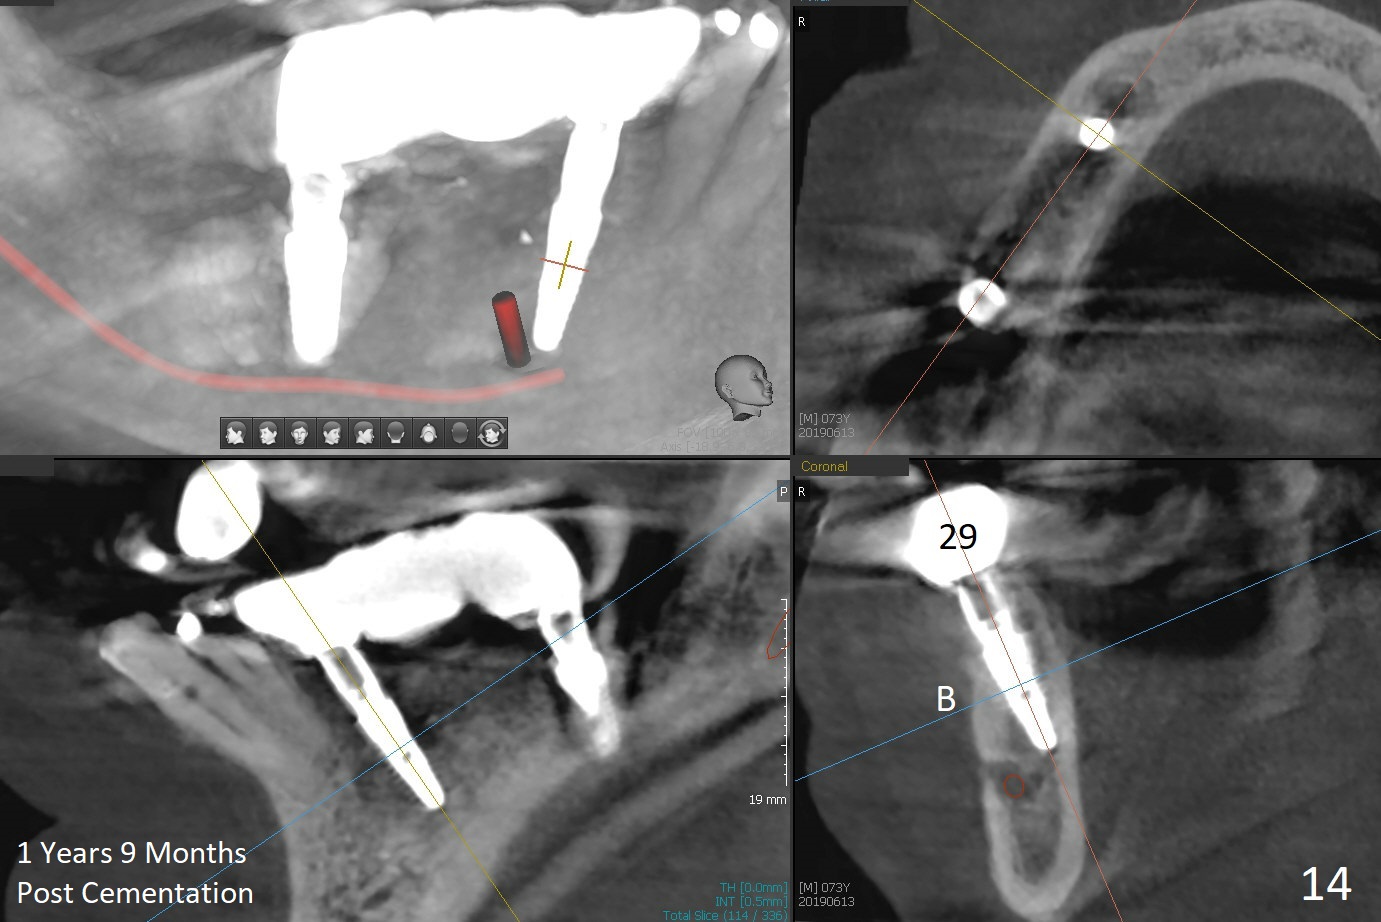

The patient will return in two weeks (total 2 months postop). The abutment at #29 will be changed to a longer one (3.9x7(6) mm). Provisional FPD will be fabricated with an emphasis to push the surrounding (especially lingual) gingiva away from the abutments, most likely using gauze as gingival retraction cord. The crown at #2 will be trimmed to have clearance. Fig.13 is taken 3 months post cementation. CBCT taken 1 year 9 months post cementation shows the uneven buccal (B) and lingual crests (Fig.14,15 arrowheads).